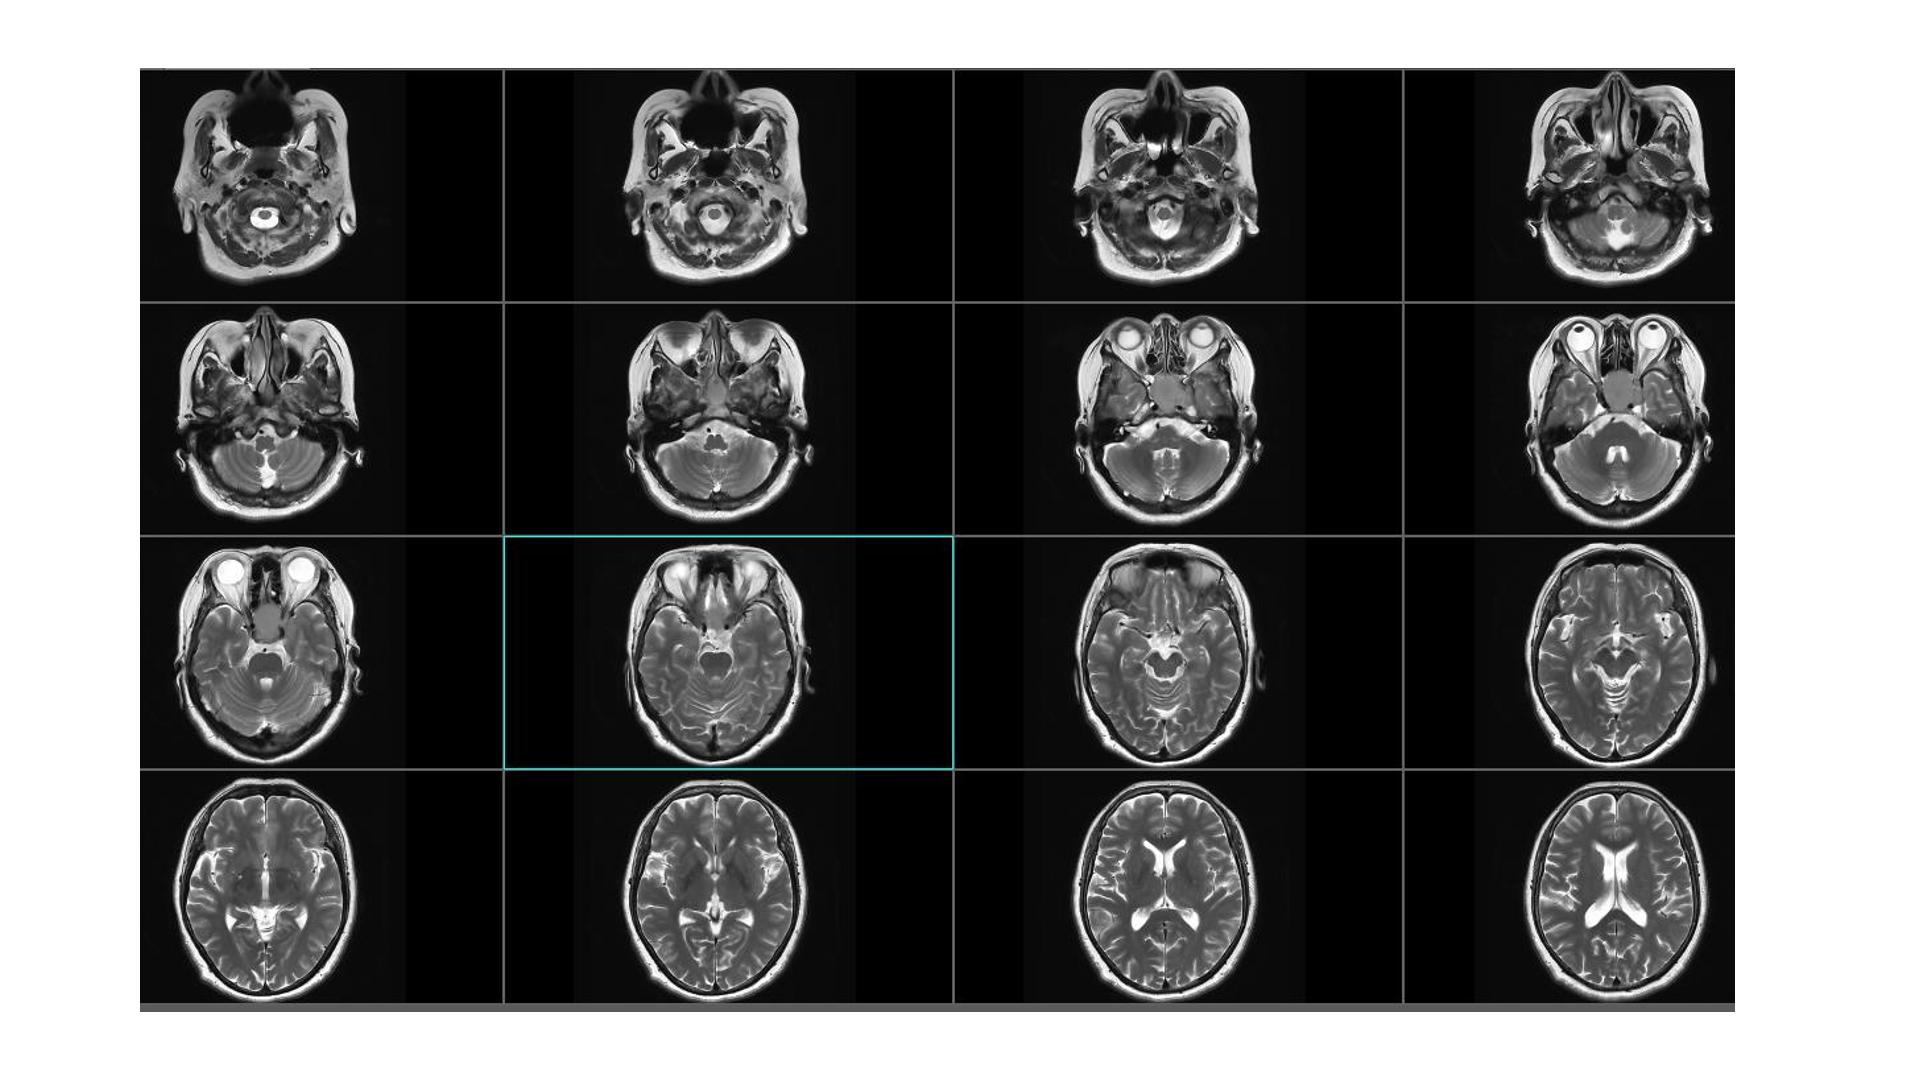

鞍区占位,蝶鞍扩大明显,侵袭海绵窦。